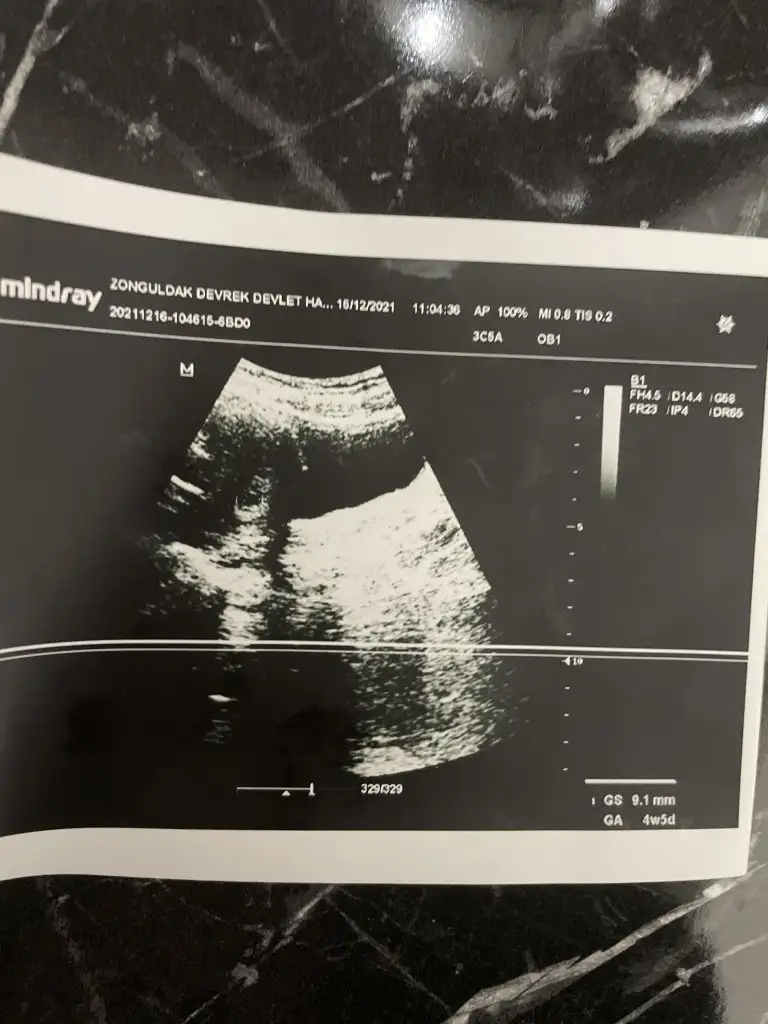

Allah razı olsun canim bebek iyi çok şükür gunde 3 kez progestan verdi agir bi is yapma dinlenmeye çalış ilişki olmasın dedi

Bu ara biraz dinlenmeyle geçirirsin bol bol su tüket oda önemli.. Parogestanı da önem amaçlı vermiştir